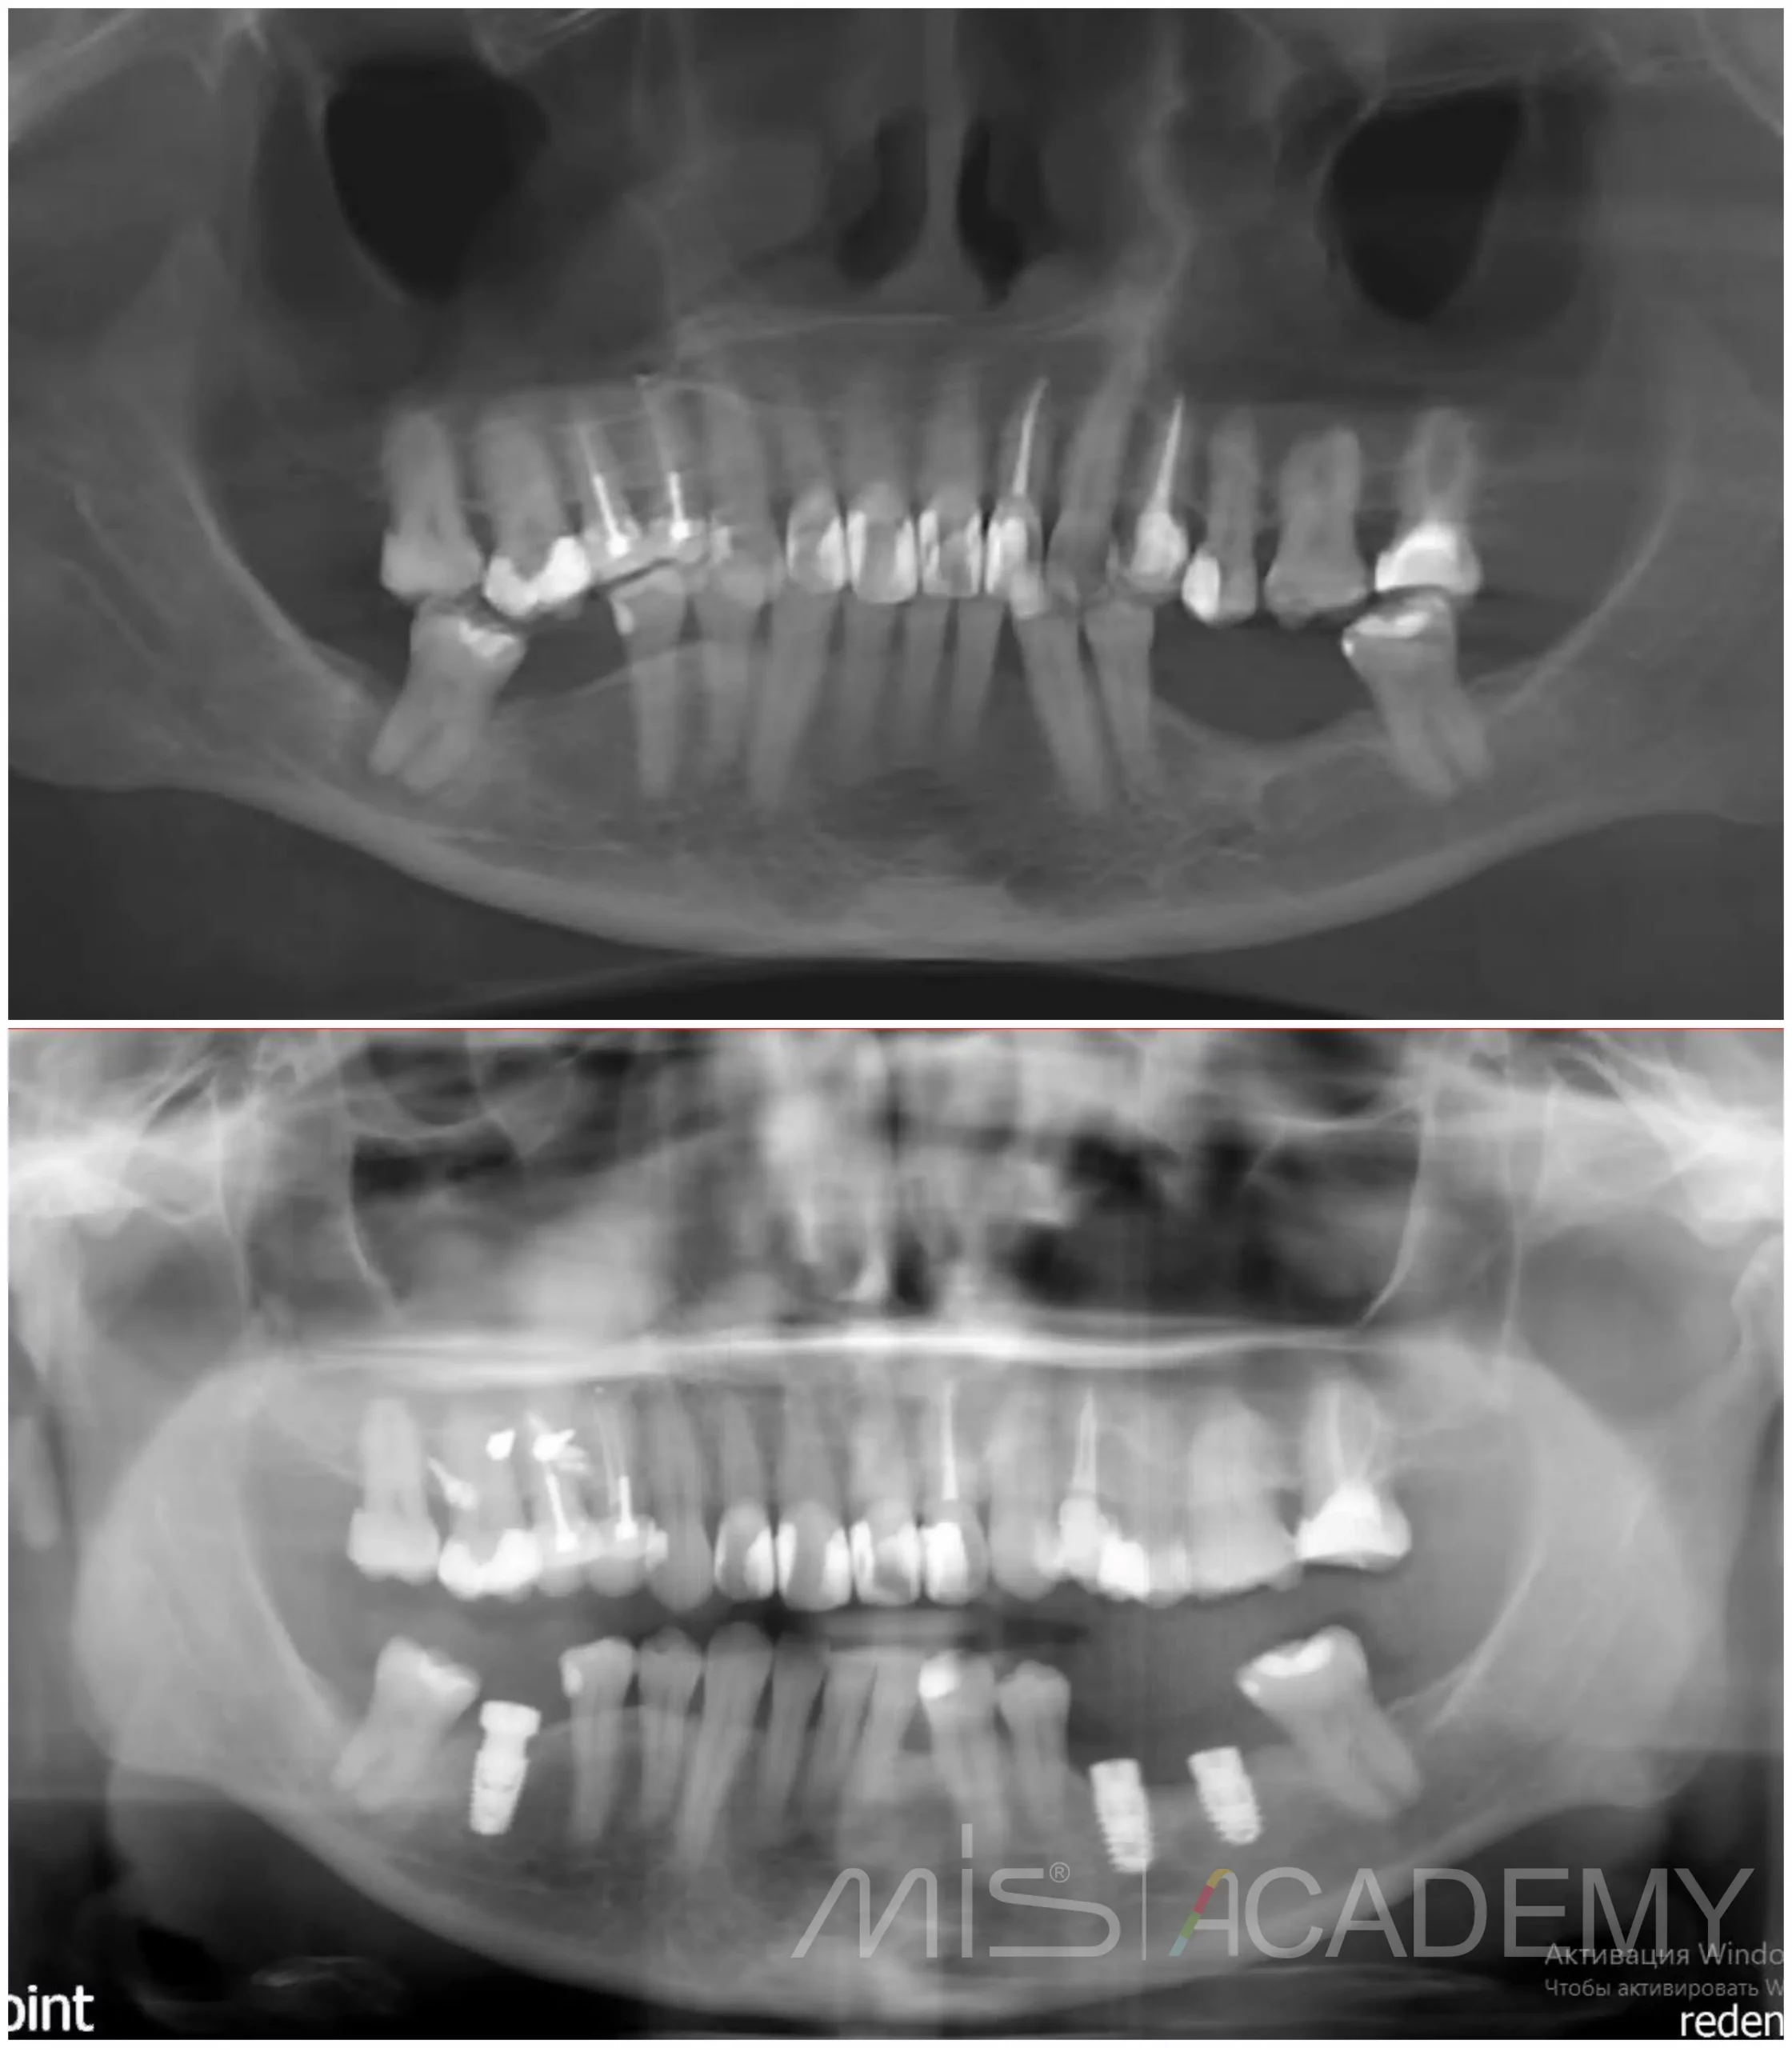

После этого Игорь Левушкин выполнил временное, а затем и постоянное протезирование.

Хороший пример того, что не каждая клиническая ситуация требует костной пластики, иногда правильное планирование и работа с мягкими тканями дают не менее стабильный и предсказуемый результат.